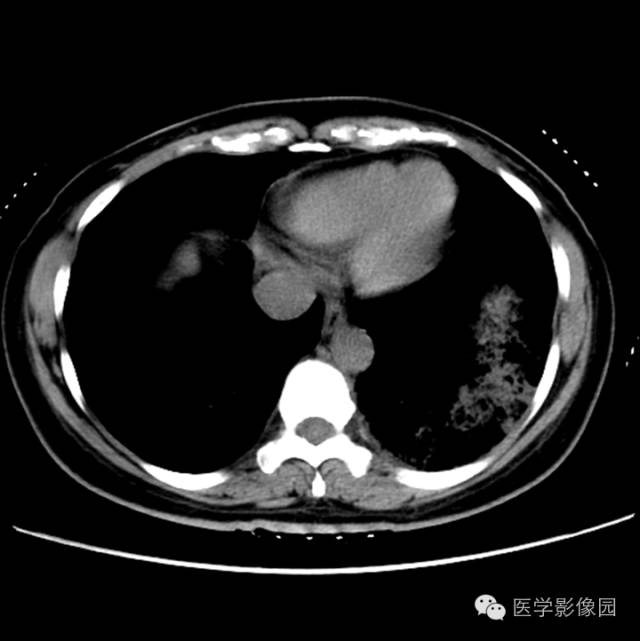

肺叶实变性支气管肺泡癌1例CT影像表现